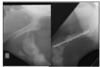

Quel énoncé est vrai par rapport à la condition sur la photo ci-dessous a) Mettre une talonette sur l’onglon à gauche dans la photo (celui affecté) b) Cette affection est généralement sur l’onglon médial du membre postérieur c) Possiblement dû à des onglons trop longs d) Phlegmon interdigité causé par F. necrophorum f) Énoncé faux

**c) Possiblement dû à des onglons trop longs**